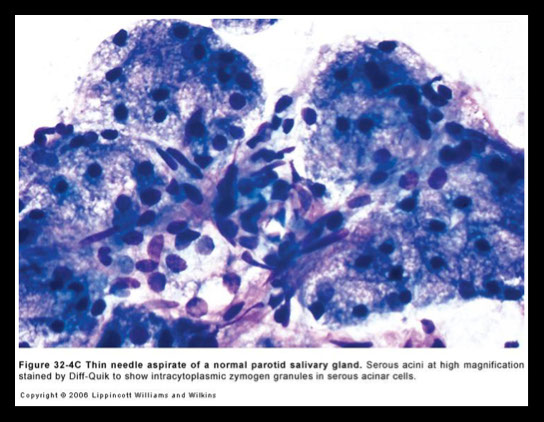

Parotid (near ear) –  Stenson’s duct

- has serous acini; proteins stored in zymogen granules

Serous glands are PAS+, c pyramidal shaped cytoplasm that is foamy to coarsely granular, small bland eccentric nuclei, with or without small nucleoli, and naked nuclei are common

Normal aspirate is hypocellular with round groups of mucinous acinar cells with vacuolated cytoplasm, flat sheets and tubules of ductal cells and fat cells